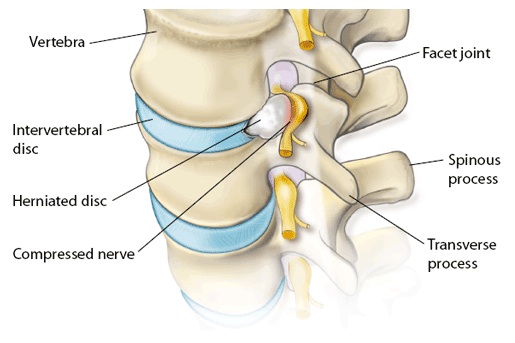

Позвонок Th10: анатомия и фото медицинских иллюстраций